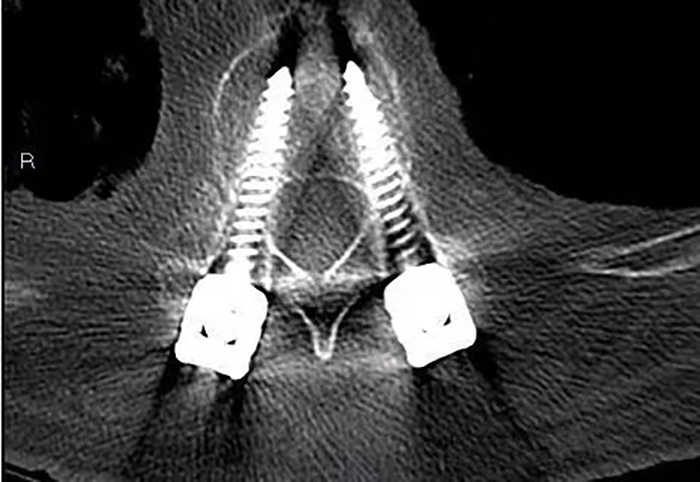

Postoperative imaging

3d printed surgical guide can effectively improve the success rate of pedicle screw placement in thoracic and spinal vertebrae. 3d printing technology provides a new treatment approach for complex spine cutting orthopedic surgery such as posterior pedicle screw implantation of cervical vertebra and upper thoracic vertebra, scoliosis protrusion deformity after orthopedic surgery, and chronic thoracolumbar fracture. 3d printing technology not only reduces the operation difficulty and risk, but also reduces the operation time, achieves forward-looking and precision, and provides personalized solutions. It also brings good news for patients to ease their pain.